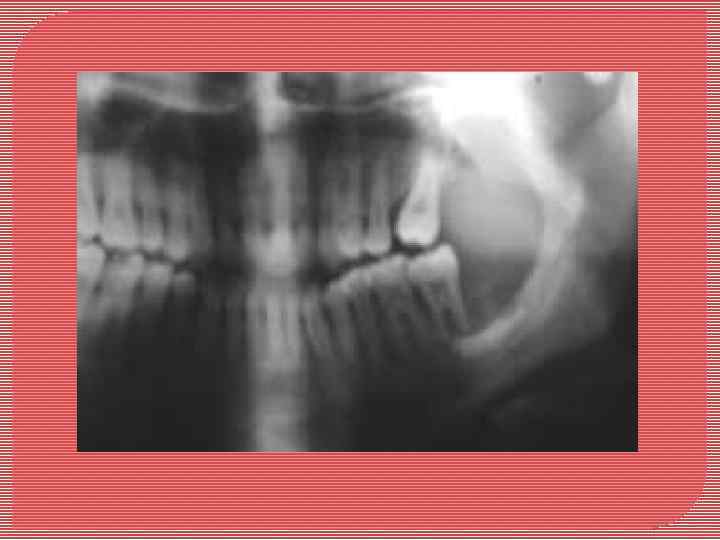

Гигантоклеточная опухоль Гигантокпеточная опухоль (остеокластоиа, остеобластокластома, бурая опухоль). Встречается в 30% случаев от всех опухолей челюстных костей. Чаще возникает у детей и молодых лиц женского пола. Локализация: область иремоляров нижней челюсти, внутрикостно. Растет медленно. Макроскопически: выбухание челюсти с подвижностью и смещением зубов и рассасыванием их корней. Кротикальный слой истончается и разрушается. Представляет собой узел от 2 до 5 см в диаметре, без четких границ, мягкой консистенции, пестрого вида на разрезе за счет чередования участков белесовато-серого цвета с темно-красными, желтоватыми, бурыми. Содержит кисты разной величины с прозрачным содержимым. Микроскопически: клеточно-волокнистая ткань с полями и гнездами опухолевых клеток двух типов: мелких, типа остеобластов, и гигантских многоядерных, типа остеокластов. Сосуды синусоидного типа или очаги «тканевого» кровотока, гемосидероз. Встречаются очаги ксантоматоза и неполноценного остеогенеза. Редко встречается злокачественный аналог гигантоклеточной опухоли, в которой анаплазии подвергаются клетки типа остеобластов.